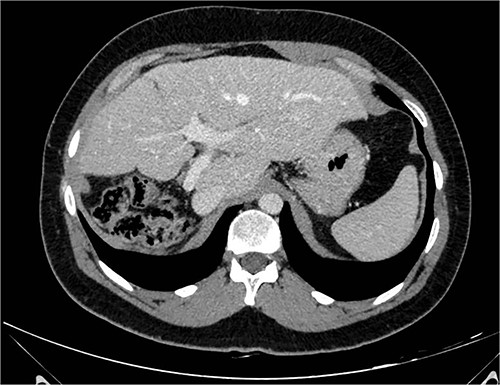

A 26-year-old, previously healthy man was admitted in March 2019 to the Surgical Department of our Hospital with abdominal distension and discomfort in the last 6 months. On physical examination, a palpable large mass was documented in the right hypochondrium extending below the umbilicus with tenderness in the upper abdomen without evidence of ascites. His medical history was little significant, just fraternal twin and hypothyroidism. Laboratory tests were carried out but tumour markers, hepatitis virus markers, and liver enzymes were normal and not diagnostic. Contrast enhanced CT-scan highlighted a giant, hypodense, heterogeneous, solid lesion without cystic component in the right lobe of the liver (Fig. 1). The tumour compressed neighbouring parenchyma and displaced abdominal organs and the retro-hepatic vena cava was also compressed with the middle hepatic vein slightly occluded by thrombotic material. Percutaneous needle biopsies were performed in different areas of the mass. All samples showed mesenchymal tissue with low proliferative index MIB1, and the pathologist suggested diagnosis of MHL. Following a thorough review of the literature, in view of the possibility of malignant degeneration and the high rate of local recurrence, radical liver surgery was proposed. Liver volumetry was measured, and the future liver remnant appeared sufficient to avoid post-operative liver failure. For this reason, liver transplantation was ruled out in favour of right hemi-hepatectomy without segment 1, according to Brisbane classification. In April 2019, the patient was admitted in operatory room after resolution of the middle hepatic vein thrombus with anticoagulant therapy. Right hepatectomy was carried out in 330 min.